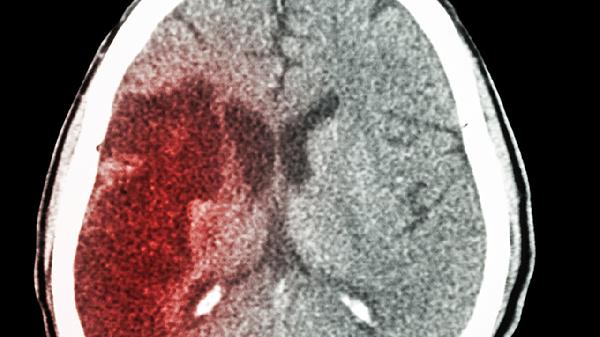

医生实地研究:脑梗患者每日散步,一年内或将迎来6大积极变化

脑梗康复路上,每天坚持散步竟能带来这么多惊喜变化!最近一项跟踪研究发现,那些出院后坚持规律散步的脑梗患者,身体状态发生了令人欣喜的转变。不用花大价钱买保健品,简单的步行就能创造康复奇.迹。